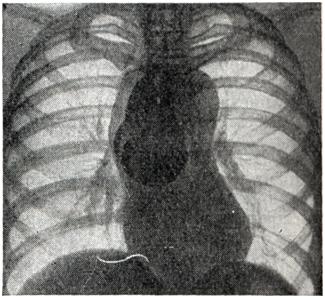

Рис. 4.

Крупная аневризма дуги аорты (рентгенограмма).

Аневризмы восходящей аорты обычно хорошо определяются в виде выпячиваний на правом контуре сосудистой тени в прямой проекции (рис. 3) и на переднем контуре — в левом косом и боковом положениях. Гораздо реже аневризма располагается на левой стенке восходящей аорты и образует выпячивание слева. Аневризмы дуги аорты (рис. 4) в прямой проекции обычно имеют вид массивной тени над изображением сердца, а в левом переднем косом положении проецируются на область дуги аорты. Аневризмы нисходящей аорты дают добавочные тени по левому контуру сосудистой тени (книзу от первой дуги) в прямой проекции и проецируются на ретрокардиальное пространство и тень позвоночника в косых положениях. Бывают множественные аневризмы аорты.